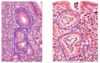

What is shown in the provided image?

What is shown in the provided image?

Chronic gastritis is too many plasma cells in the lamina propria

In H. pylori, there is a tendency for that infiltrate to be more superficial

What is shown in the provided image?

PMN infiltration of epithelium and gastric glands

acute inflammation on top of chronic gastritis

more common with H. pylori